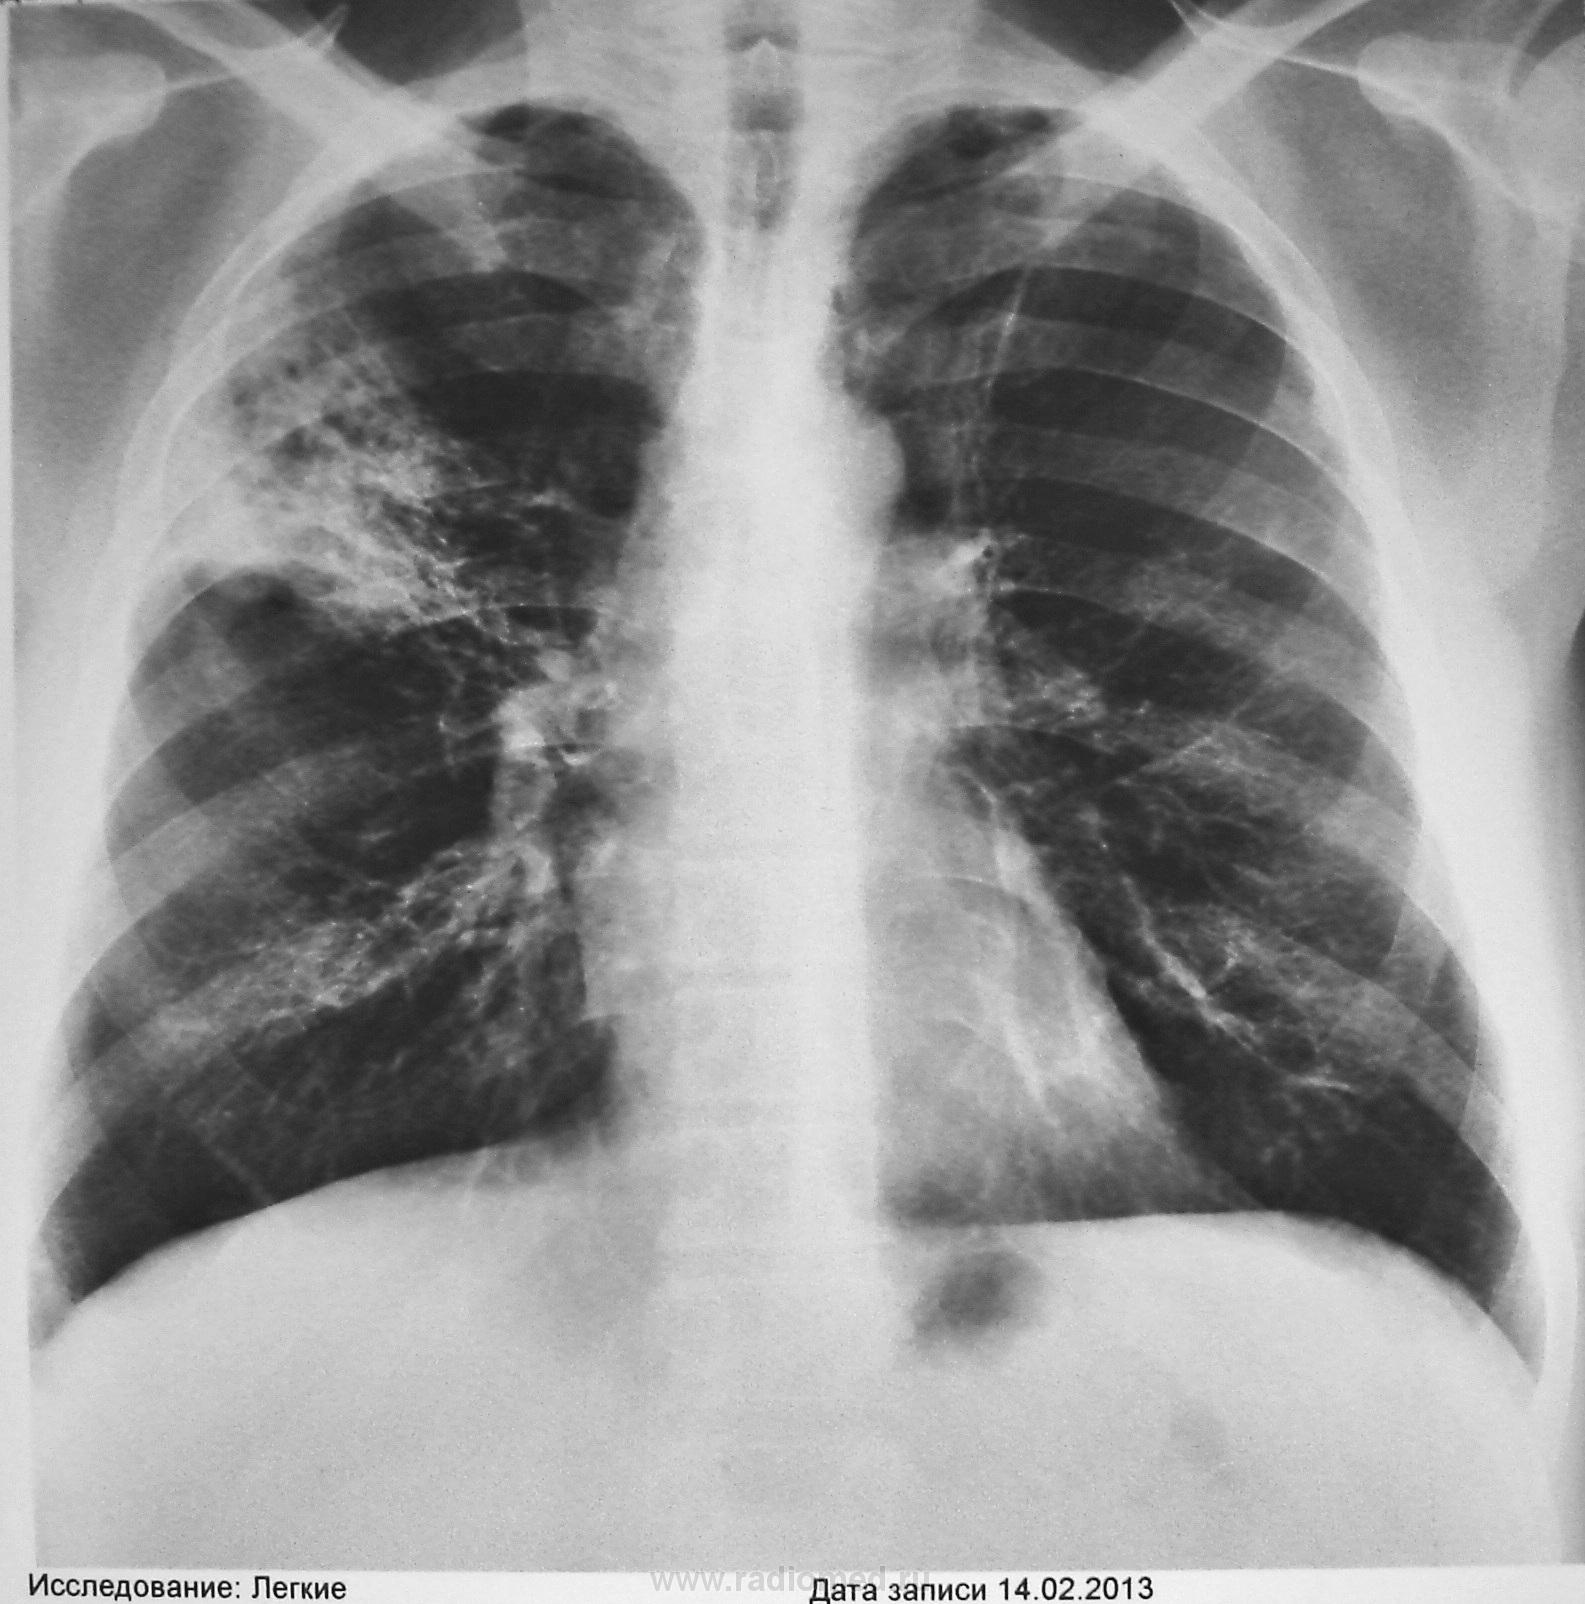

50 л. Кашель, слабость, t-37,0. в течение 2-х недель. При обращении к врачу сделали КТ 5.2.13 г.(см. ссылку). Лечение АБ. Контроль 14.2.13г. (см.рис.1.2.3). Ваше мнение коллеги. Диагностика продолжается.

Динамики между картиной КТ и рентгенограммой на фоне а/б лечения нет. Снижение пневматизации верхней доли справа, больше в S1, аксиллярном субсегменте, сочетание перибронхиальной консолидации и участков дольковой деструкции в плащевидной зоне, сохранение воздушной бронхограммы с деформированными стенками бронхов, минимальная реакция лимфоузлов средостения, уменьшение объёма доли. Кальцинированные лимфоузлы средостения, посттуб.изменения (очень вероятно) верхних долей.

Дифференцировать между инфильтративным туберкулезом (преимущественно верхушечный сегментарный/перициссурит), БАР и хитрой пневмонией, наподобие пневмоцистной.

Посттуберкульозные изменения тут точно есть. Левый корень тянется к верхушке, там же плевральные наслоения. Справа, учитывая более-менее ограниченую во втором сегменте локализацию, по моему мнению выраженый метапневмонический либо метатуберкульозный фиброз и такой же плеврит (реакцию плевры видно на КТ). В плане рака - хоть какой-то лимфоузел должен был отреагировать. Дальше чисто рентгенологически не угадаешь))) Нужны дополнительные методы и комплексная оценка. Пробовать бронхоскопию. Исключать реактивацию тубпроцесса.

Некоторые уточнения и дополнения. Первичное обращение пациента за медицинской помощью было в частную медфирму, где ему сразу предложили КТ ОГК. Диагноз пневмония. Лечение: цефалоспорины в/м 7 дн., далее респираторные фторхинолоны 14 дней. В ПТД пришел самотеком по рекомендации рентгенолога только с данными рентгенологического исследования (см. начало). Состояние удовлет. Отмечает улучшение состояния на фоне лечения. Одышки нет. t тела -норма. Аускультативно дыхание жесткое везикулярное. Гемограмма - норма. Контрольное КТ 28.2.13. (см. ссылку http://files.mail.ru/58492918BAA04EC2B35C460271920DF9

). В мокроте МБТ не обнаружены методом бактериоскопии. Туберкулиновых пробы - отказ пациента. От бронхоскопии пока воздерживается. Стало известно, что в 1991 г. диагностирован "саркоидоз". Лечился. Документация утеряна??!! В последующие годы флюорогрфию не проходил. Архива нет. Пока все коллеги. Других материалов нет.

С учетом анамнеза, морфологической верификации в прошлом саркоидоза, можно предположить 4 стадию заболевания (легочный фиброз), либо - атипичную форму саркоидоза.